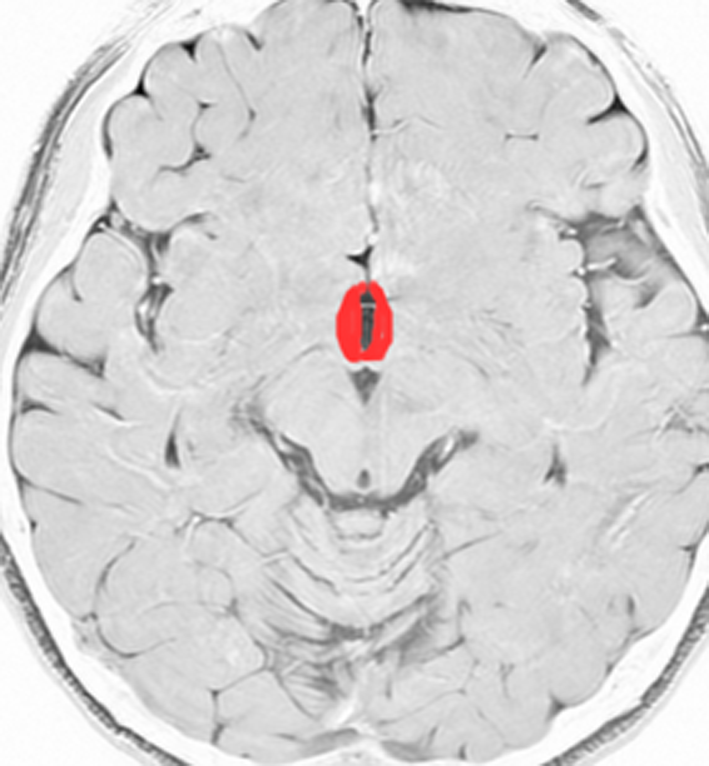

視床下部と下垂体の図です

赤く塗ってあるところが視床下部と下垂体です。ここには体の中にホルモンを分泌する働きの中枢があってとても大切な場所です。上の方が視床下部で,下に垂れ下がっているようなのが下垂体です。

赤く塗ったところが視床下部と下垂体です

視床下部は下垂体の上位中枢で,下垂体は視床下部の命令で機能しています